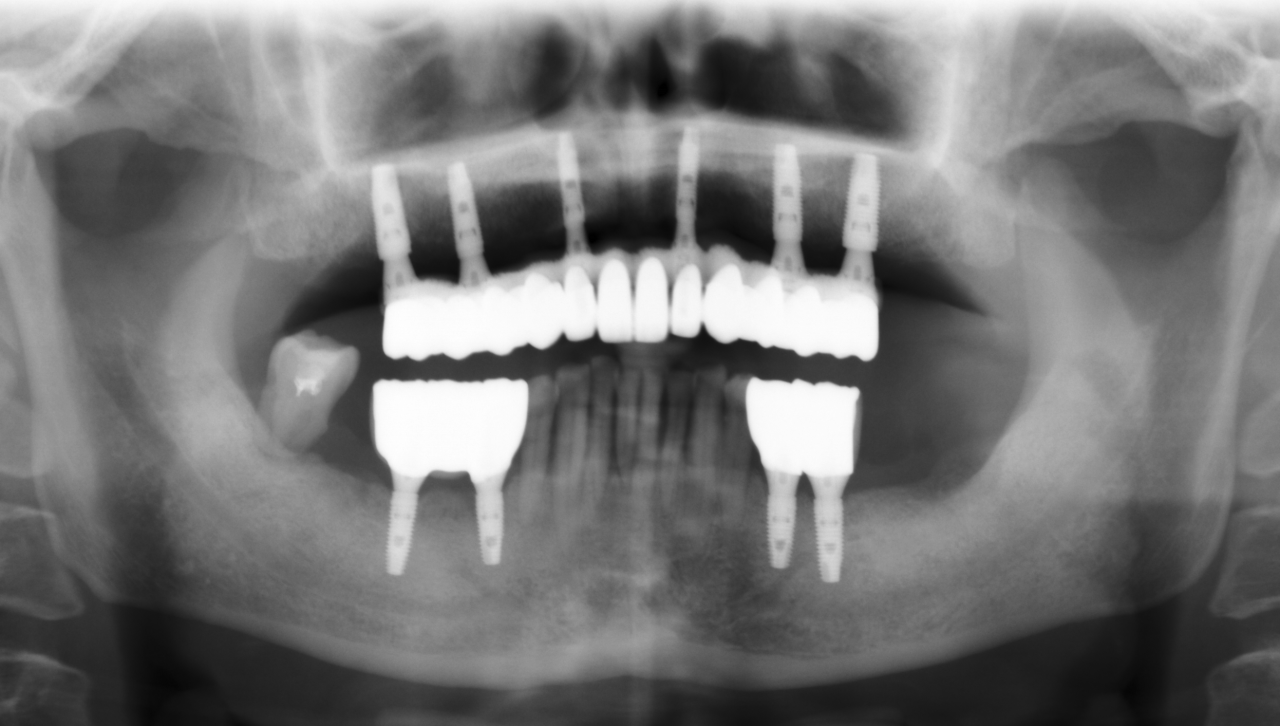

永久修复3年随访:

上下颌边缘骨稳定,零骨吸收

通过修复后口内照观察到,美学效果良好,无基台种植体配合性能相关的周围炎。通过医学影像观察到,修复三年后种植体周围无骨吸收,患者非常满意。